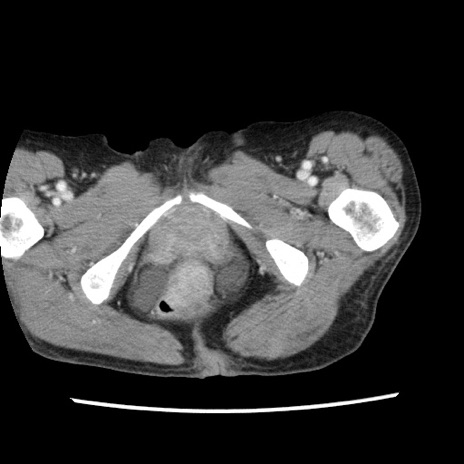

症例1(横断像)

【症例】80歳代女性

【主訴】腹痛

【現病歴】8時間前から腹痛あり来院。

【既往歴】糖尿病、脂質異常症、子宮体癌にて子宮全摘術

【身体所見】意識清明・会話良好だが腹痛で苦悶様、全腹部にわたって反跳痛と圧痛あり

【データ】WBC 13600、CRP 0.14、LDH 224、CK 90